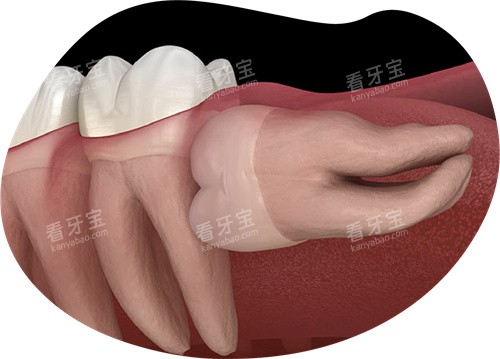

3.2 牙齿拔除价格

拔牙价格因牙齿类型和拔牙难度而异:

阻生智齿拔除:500元起

但如果牙齿完全萌出,位置正常,拔除难度相对较小,费用通常在300-500元。

若智齿阻生,特别是低位阻生,价格可能会升至800-1500元。

复杂的阻生智齿拔除,如果需要切开牙龈、去骨等操作,费用可能达到1000-3000元。